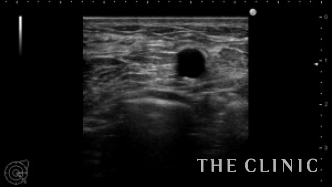

左乳腺下にオイルシストが2個ありました。

エコー下に穿刺吸引しました。

白濁したオイルが引けました。この後、コンデンスリッチ豊胸を行いました。